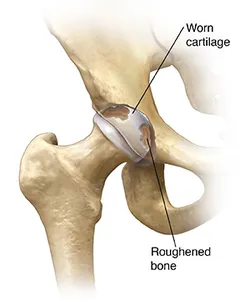

A problem hip

In a problem hip, the worn cartilage no longer serves as a cushion. As the roughened bones rub together, they become irregular, with a surface like sandpaper. The ball grinds in the socket when you move your leg, causing pain and stiffness.